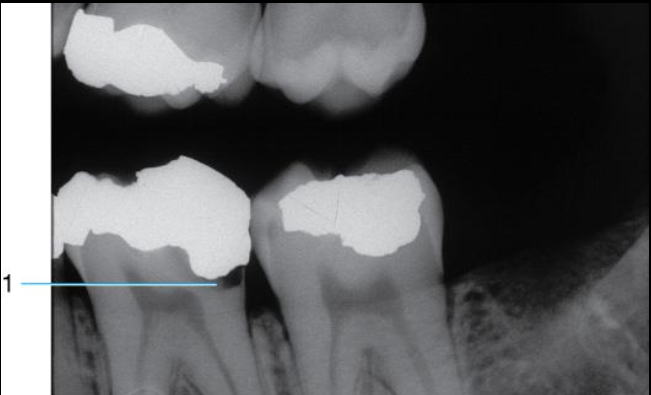

3 Criteria for a bite-wing exposuresÂ

What does #1 show?

#1 shows INCORRECT vertical angulation

it is over angulated thus obstructing the interproximal view of the lesion

#2 shows CORRECT vertical angulation

interproximal caries now visible on the radiograph.

**vertical angulation = tilting PID up or down